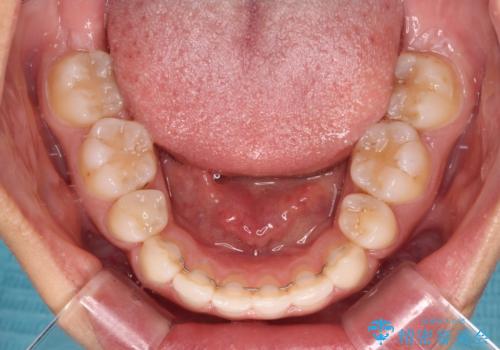

2年から2年半の治療期間を想定しており、予定通りの期間で無事に終了することができました。

唇や顎先に力を入れないなくてもスムーズに唇を閉じることができるようになりました。